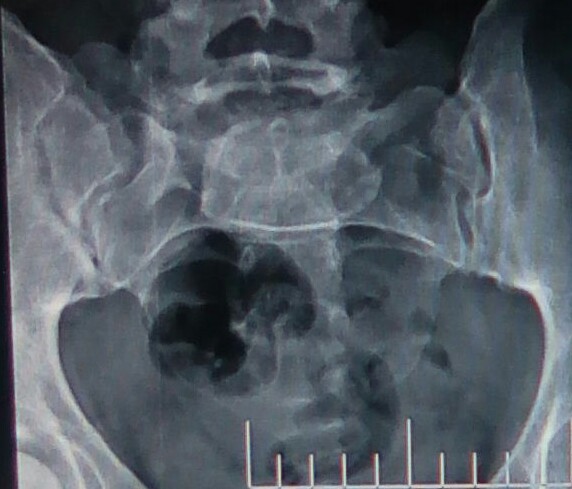

Ho una malformazione genetica rara nella zona sacro illiaca?

Quale è il nome di questa malformazione?

Non riesco a rintracciare il medico che mi diagnosticò a voce questa problematica ed altri dottori non vedono nulla. Ho qualcosa o non ho niente da questa lastra ? Mi fa male questa parte, almeno per dare un nome al mio dolore.

Commento file: Questa è la mia lastra zona sacro illiaca.